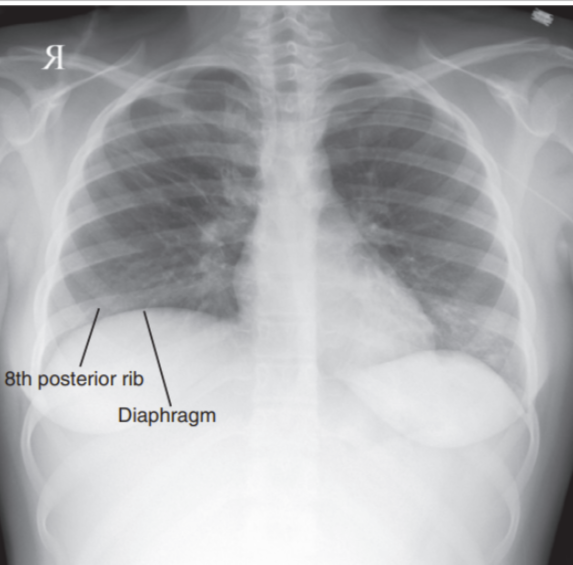

Inspiration did not occur, lungs are not filled with air

Lungs without full aeration